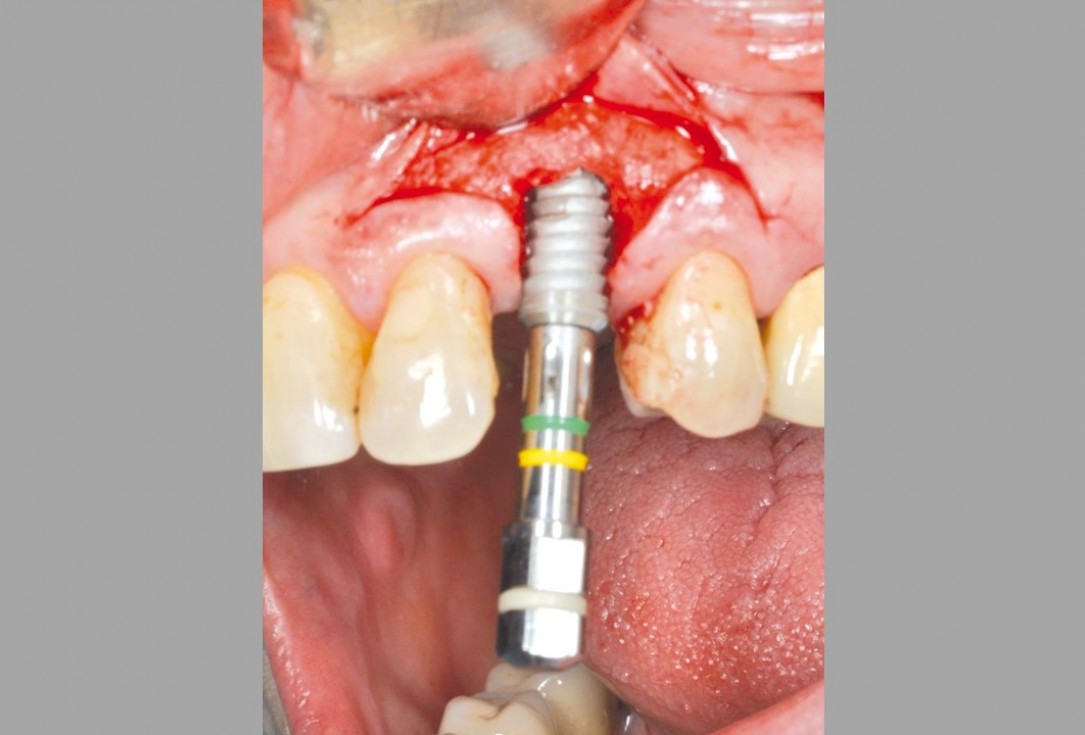

botiss cerabone® & Jason® membrane for GBR - Clinical case by Dr. S. Kovalevsky

Implant insertion in atrophic alveolar ridge